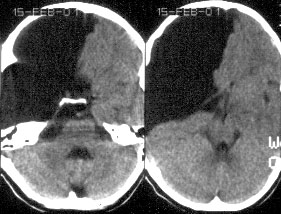

Симптомы: гидроцефалия наблюдается у >90% больных с аномалией Дэнди-Уокера и, поэтому основными симптомами в раннем детском возрасте будут симптомы прогрессирующей гидроцефалии. Диагноз подтверждается путем проведения КТ или МРТ (предпочтительнее) головного мозга.